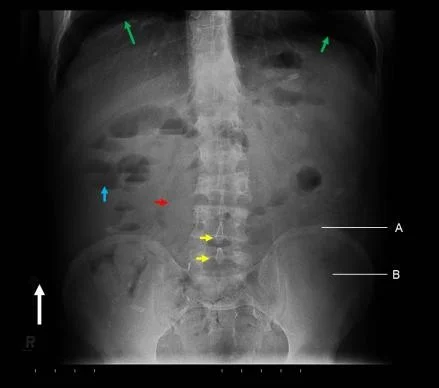

Soft Tissue Reading

- In relation to bone cortex

- Next to bone

- e.g. fat pad

- Muscles

- Muscle planes, bulk

- Other soft tissues

- Vessels, lungs, organs, cartilage

- Calcifications, Air, Fluid, âŚ

Look for the Unexpected

- Minor narrowing of the subacromial space (arrowheads) - suggesting rotator cuff disease - very common cause of shoulder pain

- It would be easy to consider this the only abnormality if not checking the image systematically

- Unexpected apical lung mass!

- Clinically suspected rotator cuff disease

- Pain distal to the elbow - rarely if ever caused by shoulder pathology

- Diagnosis

- Minor rotator cuff disease

- âPancoastâ tumour - apical lung cancer (cause of distal pain - referred from brachial plexus)